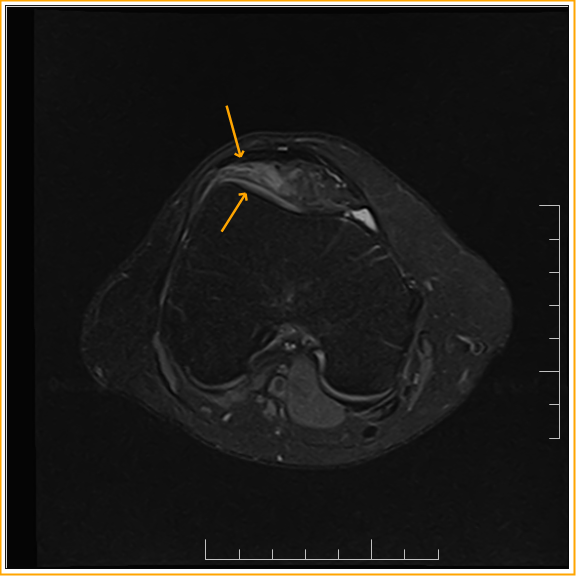

From radiopaedia.org

Anterior suprapatellar fat pad impingement syndrome Image Fat Pad Impingement Knee Symptoms Patellofemoral crepitus might be present, with. Hoffa’s fat pad impingement syndrome (also known as infrapatellar fat pad impingement) occurs when a fat pad in your knee gets pinched between the bones of your. Symptoms of fat pad syndrome are anterior knee pain, often retropatellar and infrapatellar. If the fat pat behind your kneecap becomes pinched between the bones of your. Fat Pad Impingement Knee Symptoms.